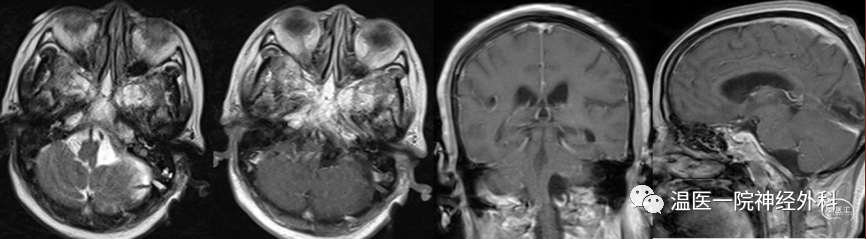

图6 术后MRI显示肿瘤完整切除。

该例枕骨大孔区脑膜瘤,主要位于枕骨大孔缘的上方。根据Bruneau等人的分型,按涉及硬脑膜腔隙归为硬膜下型;按肿瘤基底部在硬脑膜的位置归为腹外侧型;按肿瘤与椎动脉的关系归为椎动脉上型。另外,按肿瘤占据枕大孔内径大小分类,属于中型枕大孔区脑膜瘤(肿瘤占枕大孔内径的1/3-1/2)。肿瘤位置靠脑干的外侧方,向内挤压脑干。这样的位置和大小给从后下方向前的手术留出了一个比较舒服的天然通道。所以我们采用直切口方式的“改良”远外侧入路,术中开颅显露至枕髁后缘,无需进行磨除枕髁,也不需要完全显露出椎动脉V3段,即可比较好地显露肿瘤。由于枕大孔区的脑膜瘤主要由椎动脉、枕动脉及咽升动脉分支供血,一般术中出血可控。因此,即使手术初期仅离断部分肿瘤基底,行肿瘤内减容术时也较少出血。随着手术进行,脑脊液的释放,手术通道会逐渐开放,最后留给术者从容处理基底及脑干侧的空间。“改良”远外侧入路较大简化了远外侧开颅过程,降低了椎动脉术中误伤的可能性,当然也对寰枕关节的稳定性不产生任何影响。另外肌肉损伤较小,肌肉萎缩及皮下积液的并发症较少,恢复相对快。